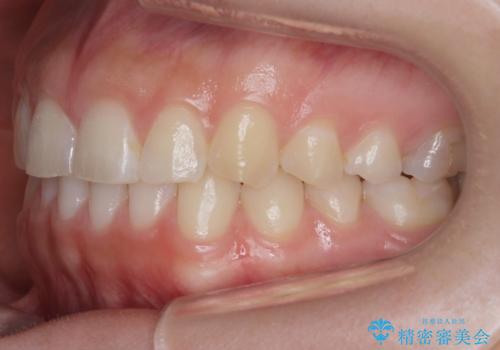

下の前歯のちょっとしたがたつきを治したい

- 下の前歯のがたつきを治したいとのことでした。

上の前歯のちょっとしたねじれも治療しています。

軽度だったため、部分矯正のコースで短期間で治療しました。

下の歯並びを並べるため、わずかに歯を削合しています。

そうしないと、前に出て上の前歯に強く当たってしまうためです。また、後戻りを防ぐ効果もあります。

年齢を重ねてくると、下の前歯が目立つようになるので治療しておくと若々しい印象を保つことができます。